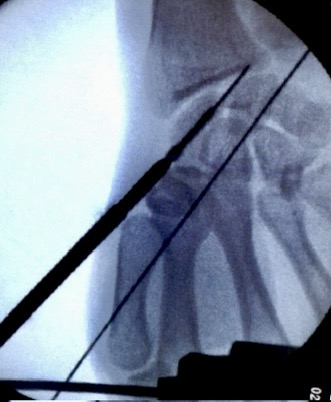

1)以Lister结节为中心做3~4cm直切口,游离拇长伸、桡侧腕长短伸牵向桡侧,纵行切开舟月关节浅面的腕关节囊,显露骨折,1.0克针临时固定。

2)完全屈曲腕关节,充分显露舟骨近极,自近极尖端,沿舟骨中轴(向掌侧和桡侧方向,与外展拇指的方向一致)钻孔,置入Herbert钉,埋入关节软骨下。(注意:螺丝钉指向舟骨掌桡侧结节部)

3)适用于舟骨近侧1/3骨折,屈腕切开关节囊,看到舟骨近极和舟月联合。螺丝钉入点尽可能靠近舟月韧带,稍偏于拇指列掌侧。

逆行法入路空心钉自近端打入